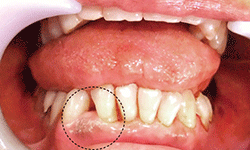

図❶ 初診時の口腔内写真

口腔内所見:32歯間の離開を認めた(図❶)。両歯とも電気歯髄診にて反応があり、生活歯であった。周囲歯肉に異常所見はなく、歯牙の動揺や自発痛・打診痛も認めなかった。また、右下唇およびオトガイ部の知覚異常もなかった。